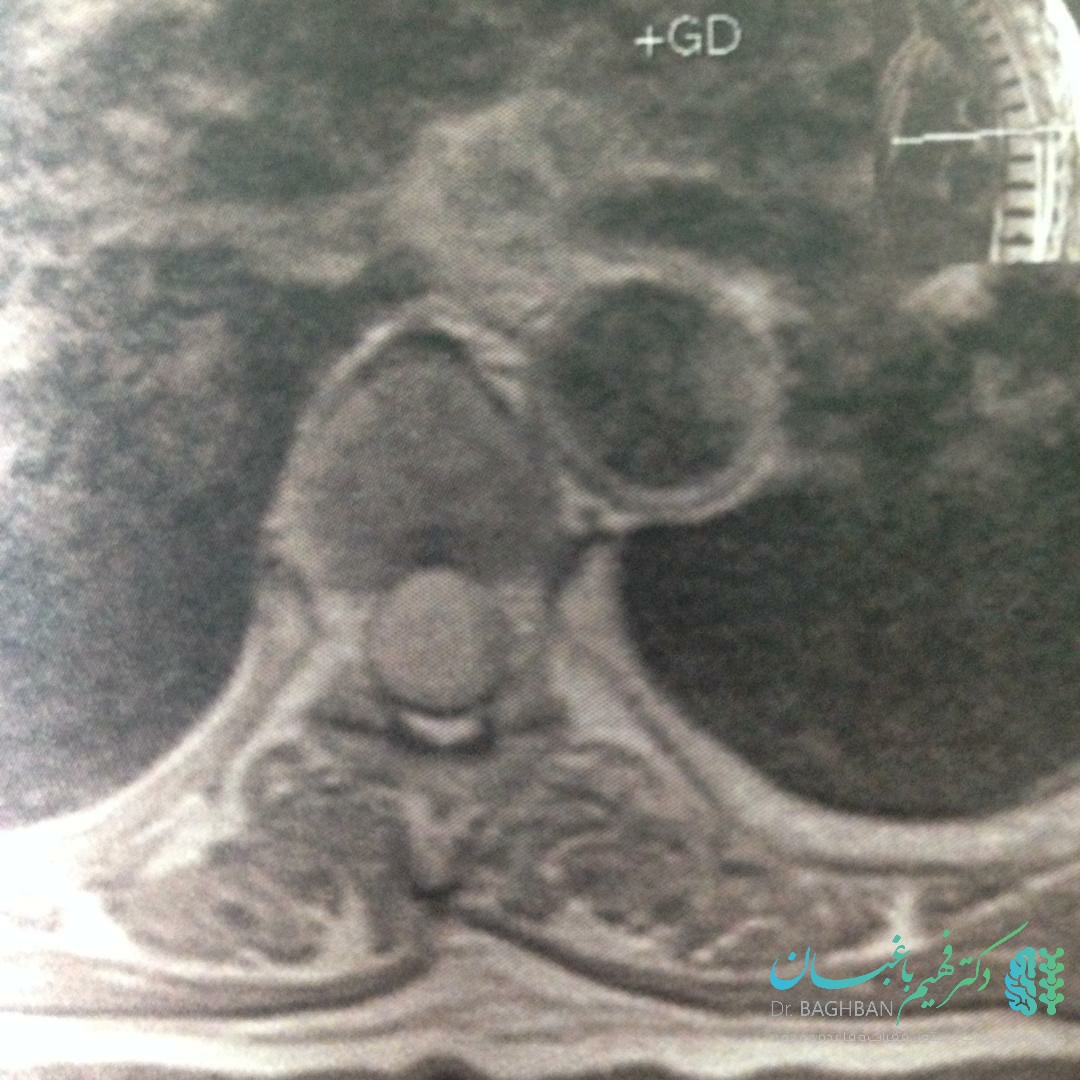

ام ار آی تومورمننژیومای نخاع پشتی

ام ار آی تومور مننژیومای نخاع